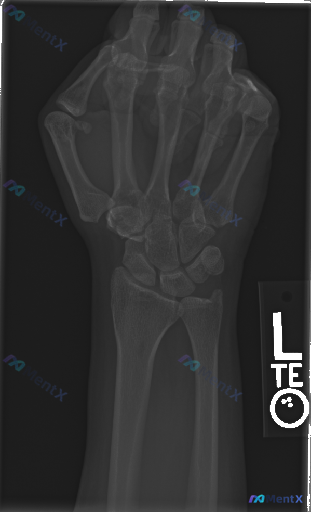

- 腕骨(舟骨、月骨、三角骨等)序列、形态大致正常,未见明确骨皮质中断或错位;桡骨远端、尺骨茎突、掌骨基底部也未见明确骨折线。

- Gilula三条弧线走行光滑连续,舟月间隙、月三角间隙未见明显增宽;桡腕关节、下尺桡关节对位尚可。

- 骨小梁清晰,无明显骨质疏松、骨质破坏或退行性变征象;关节周围软组织轮廓自然,无局限性肿胀或异常高密度影。

目前影像结论: 本次检查未见腕骨或前臂远端骨折、脱位或明显的关节结构异常征象。